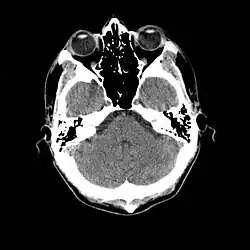

- 1976

- Cranial computed tomography (CT, invented 1972) proved to be an excellent tool for diagnosing cerebral neoplasms in children, including those found in tuberous sclerosis.[46]

- 1987

- MR was judged superior to CT imaging for both sensitivity and specificity. In a study of fifteen patients, it identified subependymal nodules projecting into the lateral ventricles in twelve patients, distortion of the normal cortical architecture in ten patients (corresponding to cortical tubers), dilated ventricles in five patients, and distinguished a known astrocytoma from benign subependymal nodules in one patient.[53]

- MR imaging was found to be capable of predicting the clinical severity of the disease (epilepsy and developmental delay). A study of 25 patients found a correlation with the number of cortical tubers identified. In contrast, CT was not a useful predictor, but was superior at identifying calcified lesions.[54]